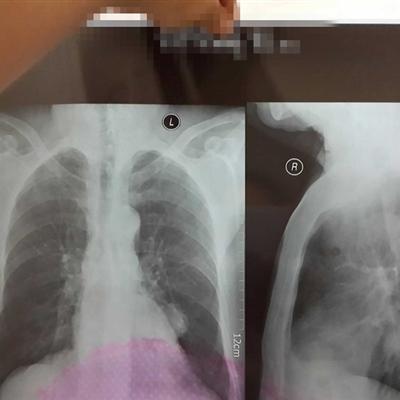

We know that the living habits of many friends in life are not particularly healthy, and the body will become worse and worse. Pulmonary sarcoidosis is a stubborn disease, which often involves multiple organs of the body, causing great harm to the body. How to treat nodules in the lung? Let me tell you.

How to treat nodule on lung